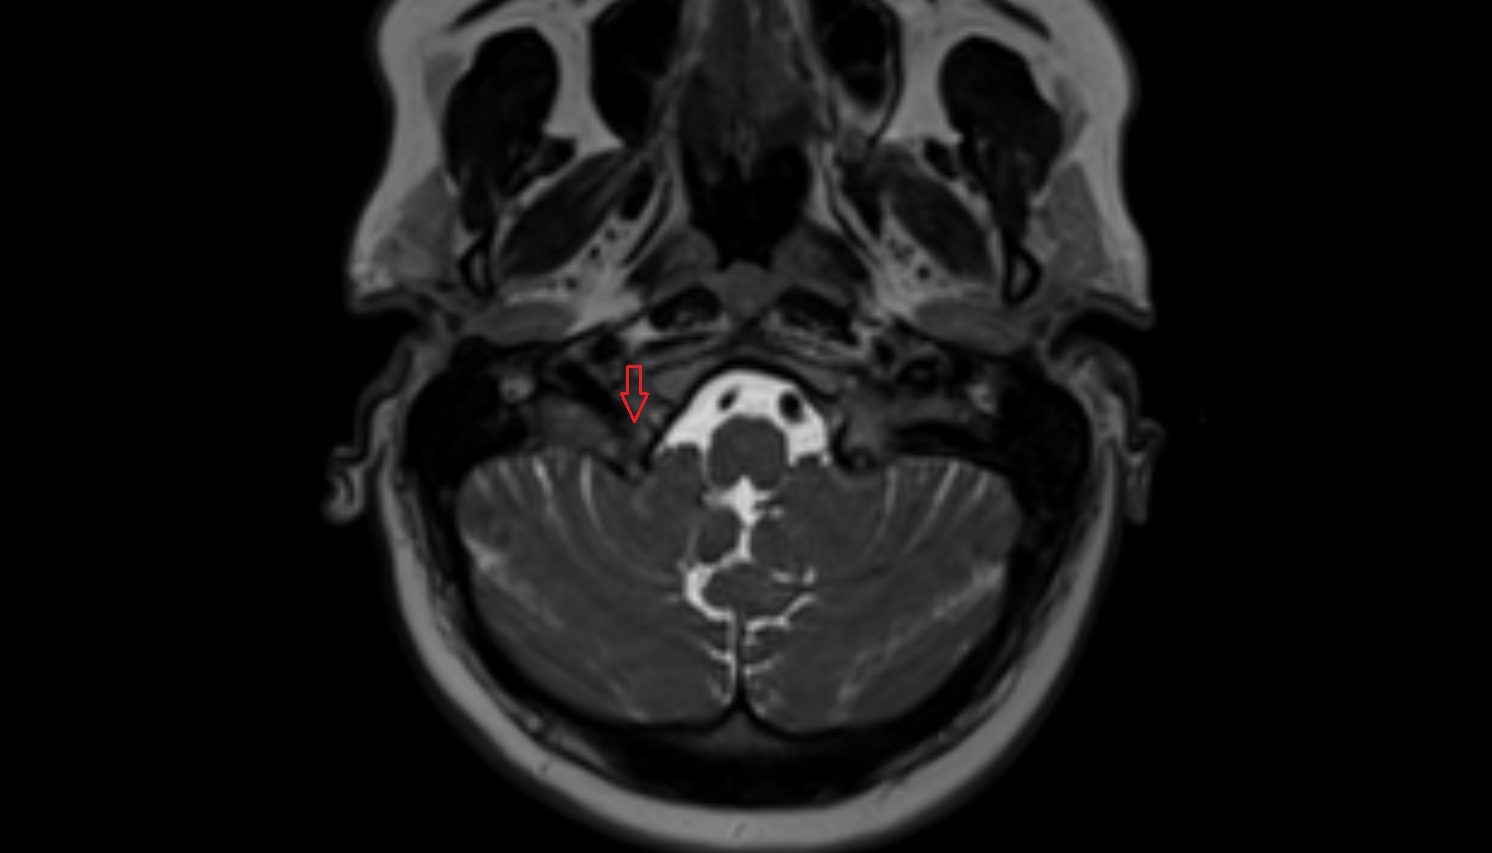

- Median aperture of fourth ventricle (foramen of Magendie)

- Lateral aperture of fourth ventricle (foramen of Luschka)